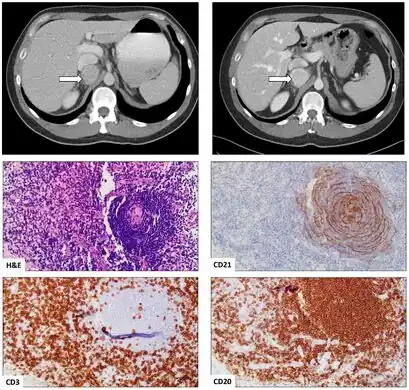

Female was found to have a mass in the retroperitoneal space deep to the inferior vena cava on CT scan; mass was biopsied and demonstrated the HV variant of UCD(CT scans at presentation and 6-year follow up)[5] -

Appearance of hyaline vascular type Castleman's disease (histology)

The microscopic appearance (histology) of biopsied tissue from an enlarged lymph node must demonstrate a constellation of features consistent with Castleman disease. There are three patterns of characteristic histologic features associated with UCD:[6]

- Hyaline vascular - regressed germinal centers, follicular dendritic cell prominence or displasia, hypervascularity in interfollicular regions, sclerotic vessels, prominent mantle zones with an “onion-skin” appearance.

UCD most commonly demonstrates hyaline vascular features; however, plasmacytic features or a mixture of both hyaline vascular and plasmacytic features may also be seen in UCD lymph nodes.[4] The clinical utility of subtyping Castleman disease by histologic features is uncertain, as histologic subtypes do not consistently predict disease severity or treatment response.[6]

Staining with latency-associated nuclear antigen (LANA-1), a marker for HHV-8 infection, must be negative to diagnose UCD.[2]